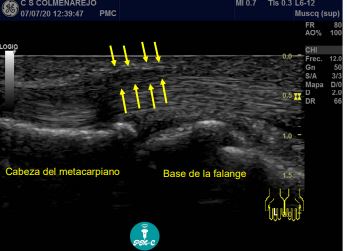

Hallazgos ecográficos

Se visualiza engrosamiento hipoecoico difuso en polea A1, líquido en las inmediaciones del tendón y tendón tumefacto.